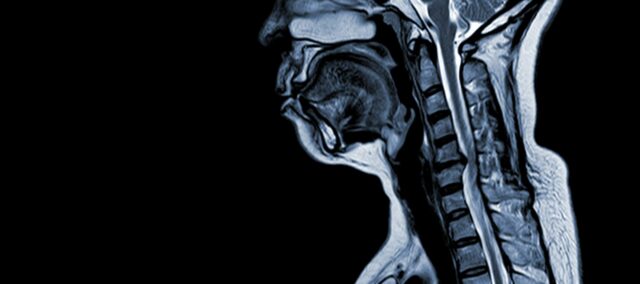

Mielopatia cervicală spondilotică (CSM) este o afecțiune neurologică care reprezintă principala cauză a leziunilor măduvei spinării la adulți. În termeni simpli, aceasta implică comprimarea sau deteriorarea măduvei spinării în gât, în principal din cauza procesului natural de îmbătrânire care afectează vertebrele cervicale. Termenul "mielopatie" provine din cuvintele grecești "myelon", care înseamnă "măduva spinării" și "pathos", care înseamnă "boală".

- Degenerarea discului (disc bombat): CSM începe adesea cu degenerarea discurilor intervertebrale din coloana cervicală, ceea ce le face să se umfle sau să iasă în canalul spinal.

- Formarea osului subperiostal (ventral față de canalul spinal): Ca răspuns la stresul mecanic crescut, organismul formează țesut osos nou pe partea din față (ventrală) a canalului spinal, îngustând astfel spațiul pentru măduva spinării.

- Osificarea ligamentului longitudinal posterior: Ligamentul longitudinal posterior poate suferi osificare, întărire și calcificare, contribuind la îngustarea canalului spinal.

- Hipertrofia Ligamentum Flavum: Hipertrofia ligamentului Flavum face ca acesta să se îngroașe și să devină mai puțin flexibil, invadând în continuare spațiul din canalul spinal și comprimând măduva spinării.

Aceste modificări structurale conduc în mod colectiv la comprimarea și îngustarea canalului spinal, rezultând simptomele și complicațiile caracteristice asociate cu CSM. Recunoașterea acestor factori de risc și înțelegerea mecanismelor fiziopatologice implicate este esențială atât pentru prevenire, cât și pentru gestionare. Diagnosticul precoce și intervențiile adecvate sunt esențiale pentru a atenua efectele acestor modificări structurale asupra măduvei spinării.